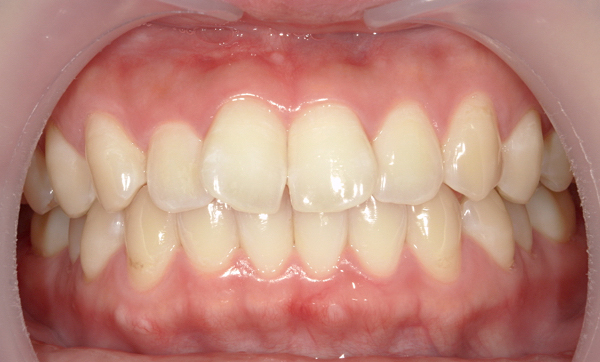

症例:上下顎の部分矯正

症例_009 前歯「八の字/V字型」症例

治療期間:11ヶ月金額:60万円+税40代女性八の字/V字型前歯のガタガタ捻転歯